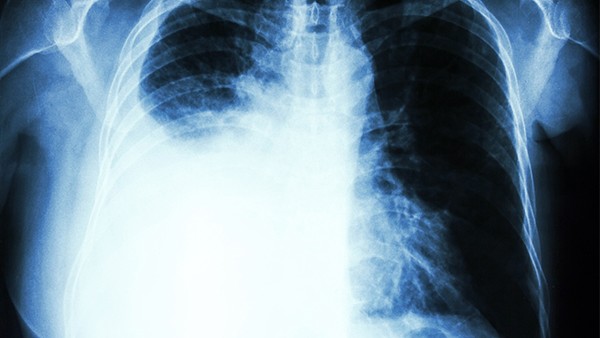

股骨骨折内固定取出时间通常在骨折愈合后12-18个月,具体时间需根据骨折类型、愈合情况及患者年龄等因素综合评估。治疗上需定期复查X光片,确认骨折线消失且骨痂形成良好,同时避免过早取出导致二次骨折。

1、骨折愈合时间:股骨骨折愈合时间受多种因素影响,包括骨折类型、患者年龄、营养状况等。简单骨折通常需要3-6个月愈合,复杂骨折或伴有严重软组织损伤的骨折可能需要更长时间。骨折愈合后,骨痂逐渐成熟,骨强度恢复,此时可以考虑取出内固定。

2、内固定取出时机:内固定取出时间一般在骨折愈合后12-18个月,具体时间需根据X光片检查结果确定。X光片显示骨折线消失,骨痂形成良好,骨强度恢复,此时取出内固定较为安全。过早取出内固定可能导致二次骨折,过晚取出则可能增加感染风险。

3、取出内固定后的注意事项:取出内固定后,患者需注意保护患肢,避免剧烈运动或负重,防止二次骨折。同时,保持良好的营养状况,补充足够的钙和维生素D,促进骨骼健康。定期复查X光片,确认骨折愈合情况,及时发现并处理可能出现的并发症。

股骨骨折内固定取出时间需根据骨折愈合情况及患者个体差异综合评估,取出后需注意保护患肢,保持良好的营养状况,定期复查,确保骨折完全愈合,避免二次骨折及其他并发症的发生。